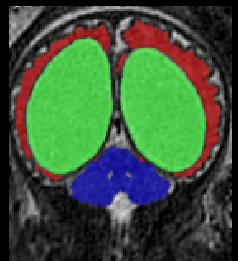

Limiting failures of machine learning systems is of paramount importance for safety-critical applications. In order to improve the robustness of machine learning systems, Distributionally Robust Optimization (DRO) has been proposed as a generalization of Empirical Risk Minimization (ERM). However, its use in deep learning has been severely restricted due to the relative inefficiency of the optimizers available for DRO in comparison to the wide-spread variants of Stochastic Gradient Descent (SGD) optimizers for ERM. We propose SGD with hardness weighted sampling, a principled and efficient optimization method for DRO in machine learning that is particularly suited in the context of deep learning. Similar to a hard example mining strategy in practice, the proposed algorithm is straightforward to implement and computationally as efficient as SGD-based optimizers used for deep learning, requiring minimal overhead computation. In contrast to typical ad hoc hard mining approaches, we prove the convergence of our DRO algorithm for over-parameterized deep learning networks with ReLU activation and a finite number of layers and parameters. Our experiments on fetal brain 3D MRI segmentation and brain tumor segmentation in MRI demonstrate the feasibility and the usefulness of our approach. Using our hardness weighted sampling for training a state-of-the-art deep learning pipeline leads to improved robustness to anatomical variabilities in automatic fetal brain 3D MRI segmentation using deep learning and to improved robustness to the image protocol variations in brain tumor segmentation. Our code is available at https://github.com/LucasFidon/HardnessWeightedSampler.